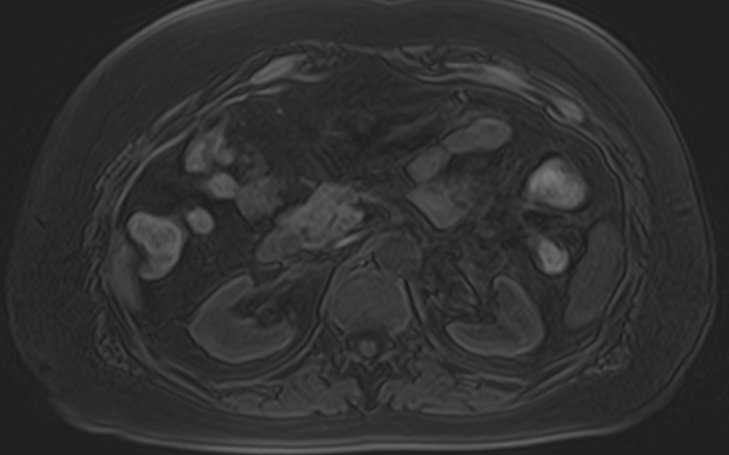

Магнитно-резонансная томография является высокоинформативным методом диагностики почечной патологии. Метод основан на применении внешнего магнитного поля без использования рентгеновского излучения, что делает процедуру безопасной для организма человека.

МРТ почек проводится для оценки состояния всех структур почек, включая паренхиму, чашечки, лоханки почек и верхние отделы мочеточников. В клинике «Доступная медицина» исследование выполняется на томографе экспертного уровня TOSHIBA VANTAGE TITAN 1,5 Тесла, который обеспечивает изображения высокой четкости и контрастности, что позволяет проводить точную и достоверную диагностику заболеваний почек.